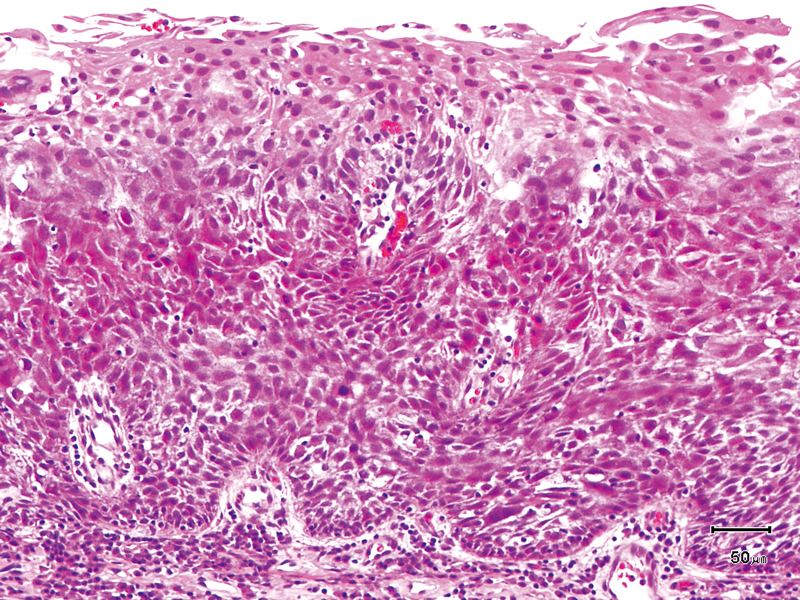

The lesion was detected on the oropharyngeal posterior wall in a periodic laryngopharyngoscopic NBI examination after an esophageal carcinoma surgery.

The NBI image showed a brownish, slightly-elevated lesion. In the conventional white light image, the same area was recognized as a slightly-whitish elevated lesion.

The lesion was treated with endoscopic mucosal resection and diagnosed as a squamous cell carcinoma in situ.